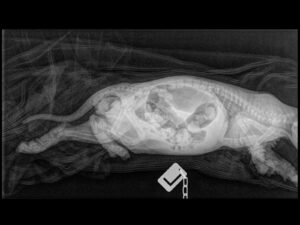

X-Rays